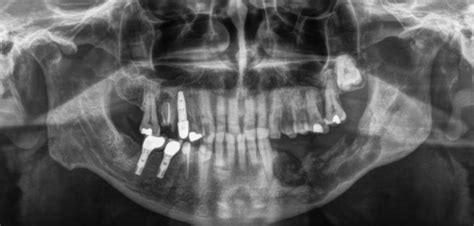

Radiografía panorámica en la que se aprecia un área de osteonecrosis (flechas) en la porción posterior de la mandíbula inferior derecha tras una exodoncia. Crédito: Banco de imágenes de la Sociedad Española de Reumatología (SER) - Dr.

Los métodos por imágenes empleados pueden ser Rx, TC o RM. En el caso de la Rx, a través de la incidencia panorámica de los maxilares, pueden apreciarse áreas de osteólisis intercaladas con zonas de esclerosis, con o sin secuestros asociados; mientras que la TC permite la visualización panorámica del maxilar inferior, detectando las áreas de erosión cortical con hueso escleroso adyacente, la proliferación perióstica, la extensión de la necrosis, los secuestros óseos y la proximidad de la lesión con respecto al canal mandibular, así como también evidencia la presencia de fístulas hacia los senos paranasales y las fosas nasales. Desde esta perspectiva, la TC permite realizar un diagnóstico más temprano que la Rx.